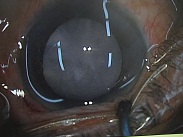

今日いらした24歳女性の症例です。

強い充血を認めます。写真の右側は、はやり目に特徴的な後遺症で、黒目(角膜)が濁っている写真です。もう少し分かりやすい、ヒドイ症例の写真を出したいのですが、ヒドイ症例は第一診察室には入らないようにしていただいたり、写真をとるなどの、余分な時間を少しでも省いて診療を行い、院内感染を予防する必要があり、なかなか難しいのです。